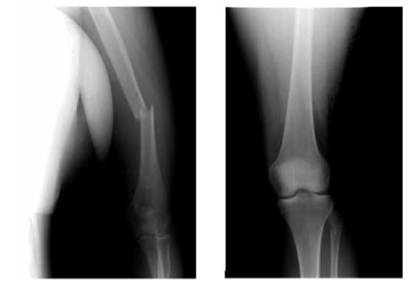

Больной Ж., 33 лет, доставлен в реанимационное отделение НИИ скорой помощи им. Н.В. Склифосовского через час после травмы - пешеход, сбит автомобилем. Осмотрен хирургом, нейрохирургом, травматологом. На основании клинической картины, рентгенографии груди, таза, нижних конечностей, УЗИ плевральных и брюшной полостей, КТ черепа и головного мозга установлен диагноз сочетанной травмы: ушиба головного мозга тяжелой степени, травматического субарахноидального кровоизлияния, разрыва правого крестцово-подвздошного сочленения, закрытого перелома правых подвздошной, лонной и бедренной костей, открытого перелома обеих костей правой голени, травматического шока II степени. При рентгенографии груди сразу после поступления правая половина диафрагмы несколько нечеткая за счет гидроторакса, расположена на уровне переднего отрезка VI ребра. Дренаж диаметром 20 Fr установлен в седьмом межреберье по средней подмышечной линии, эвакуировано 400 мл крови. После проведения интенсивной противошоковой терапии под эндотрахеальным наркозом выполнили стабилизацию переломов костей таза, бедра и голени аппаратами наружной фиксации и первичную хирургическую обработку раны голени.

Через 3 сут после травмы после стабилизации состояния и контрольной рентгенографии груди (рис. 1) пострадавший переведен на спонтанное дыхание и экстубирован, дренаж из правой плевральной полости удален. Рисунок 1. Рентгенограммы груди. а - 2-е сутки после травмы; б - 6-е сутки после травмы. Тяжесть состояния в этот момент определялась черепно-мозговой травмой и дыхательной недостаточностью I степени. При аускультации дыхание было ослаблено справа в базальном отделе. При рентгенографии на 6-е сутки после операции отмечены нечеткость контура и высокое расположение правой половины диафрагмы - на уровне переднего отрезка III ребра. При УЗИ подтверждено высокое расположение правой половины диафрагмы и обнаружен ее дефект с перемещением части печени в правую плевральную полость (рис. 2). Рисунок 2. Эхограмма правой плевральной полости на 6-е сутки после травмы. 1 - неповрежденный участок диафрагмы; 2 - печень, переместившаяся в правую плевральную полость через разрыв диафрагмы; 3 - жидкость в правой плевральной полости.

На рентгенограмме после операции правая половина диафрагмы четкая, на уровне переднего конца V ребра (рис. 4), при УЗИ свободной жидкости в плевральной полости нет, диафрагма четкая, печень расположена в брюшной полости (рис. 5). Рисунок 4. Рентгенограмма груди после операции. Рисунок 5. Эхограмма правой плевральной полости после операции. 1 - правая половина диафрагмы; 2 - печень. Послеоперационный период протекал без осложнений. Дренажи удалены на 3-и сутки после операции, раны зажили первичным натяжением.

По стабилизации состояния пострадавший переведен в травматологическое отделение. Ему был последовательно выполнен внеочаговый остеосинтез правой бедренной и большеберцовой костей блокируемыми штифтами. В удовлетворительном состоянии выписан под наблюдение травматолога по месту жительства на 62-е сутки после травмы.